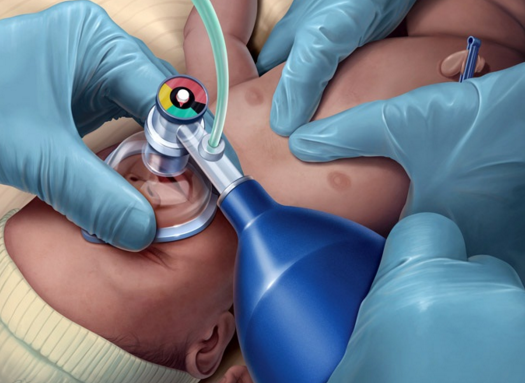

Distração e Fatores Humanos (“Dirty Dozen”) na reanimação neonatal Sobre